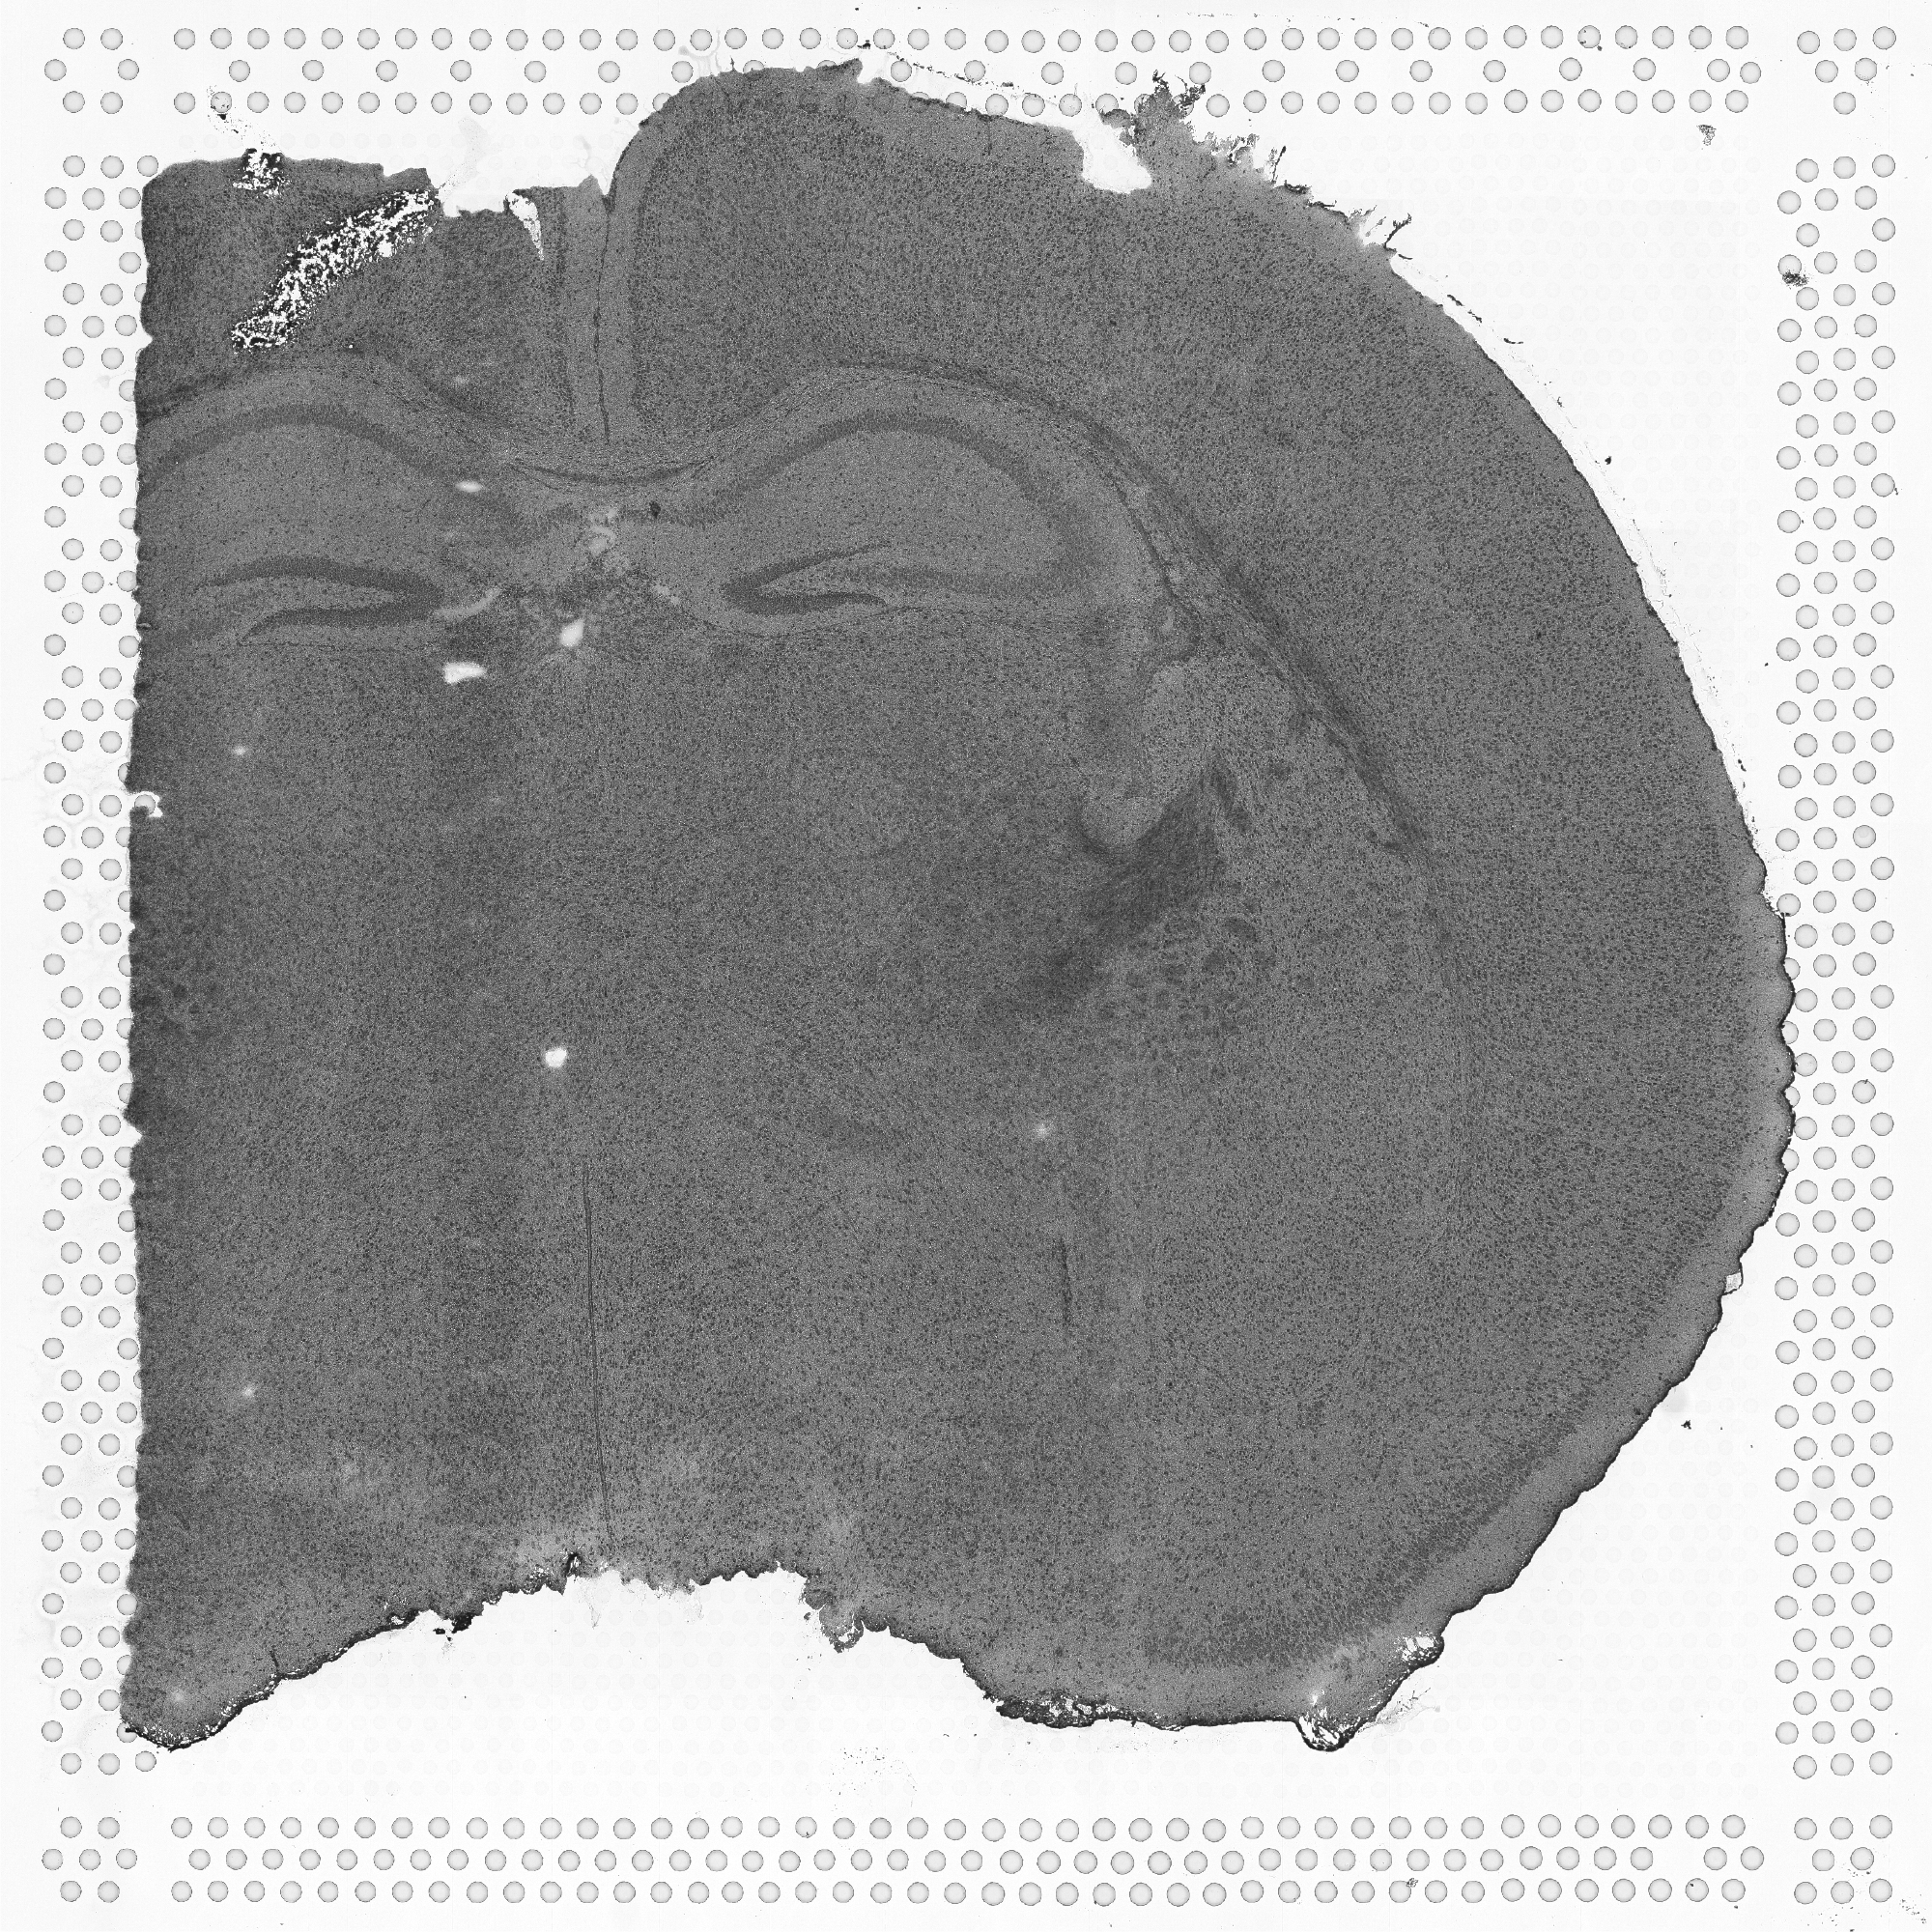

tissue_hires_image.png